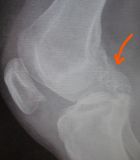

1. Popliteal extraskeletal chondroma of the right knee in a 38-year-old female.

I. Before the surgery , lateral x-ray of the knee shows the chondroma (red arrow) II. Post-surgery, lateral x-ray of the knee shows that the chondroma has been removed III. Post-surgery, the photo (posterior site of the knee) is showing the specific approach that has been used for the operation.